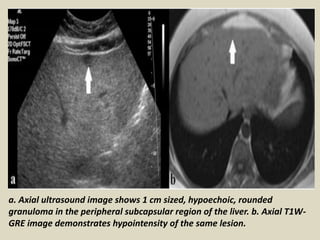

a. Axial ultrasound image shows 1 cm sized, hypoechoic, rounded

granuloma in the peripheral subcapsular region of the liver. b. Axial T1W-

GRE image demonstrates hypointensity of the same lesion.